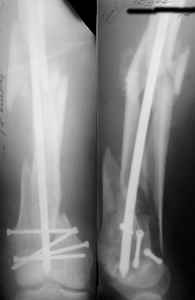

I presented a series of ~25 such cases at EuroTrauma'2004. Many cases were discussed here. I attach am example. Look also recent cases at http://www.hwbf.org/hwb/conf/alex58/scfx.htm,

http://www.hwbf.org/hwb/conf/alex63/alex63.htm

THX, initial images are

1,

2.

At that moment we had in stock only the 10 mm solid nails so of course there was no idea about early weight bearing. But it was quite enough for early knee ROM excersises (see attached). Two locking screws through the distal block provided that.